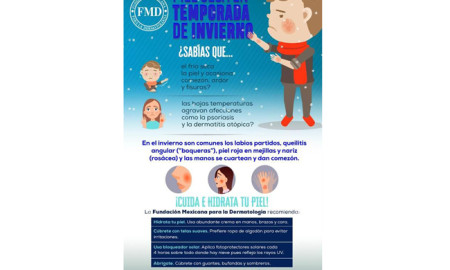

1.4KSalud y nutriciónLas bajas temperaturas deshidratan la piel, hay que tener cuidados especiales: FMD

Recomiendan bañarse con agua tibia y jabones neutros. Menores y adultos, los grupos más vulnerables.